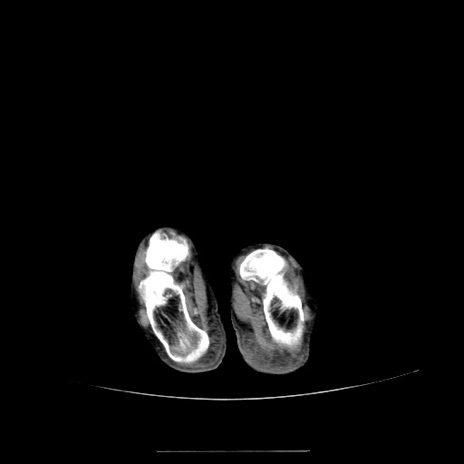

【症例】70歳代女性

【主訴】お腹が張る

【現病歴】1週間くらい前から腹部膨満の自覚あり。昨日夜から増悪したため、本日救急外来受診。

【身体所見】意識清明、BT 36.5℃、BP 165/106mmHg、HR 80bpm、SpO2 98%、腹部:膨満、軟、自発痛・圧痛なし、触診にて不快感あり、腸蠕動音:減弱

【データ】WBC 12600、CRP 1.04